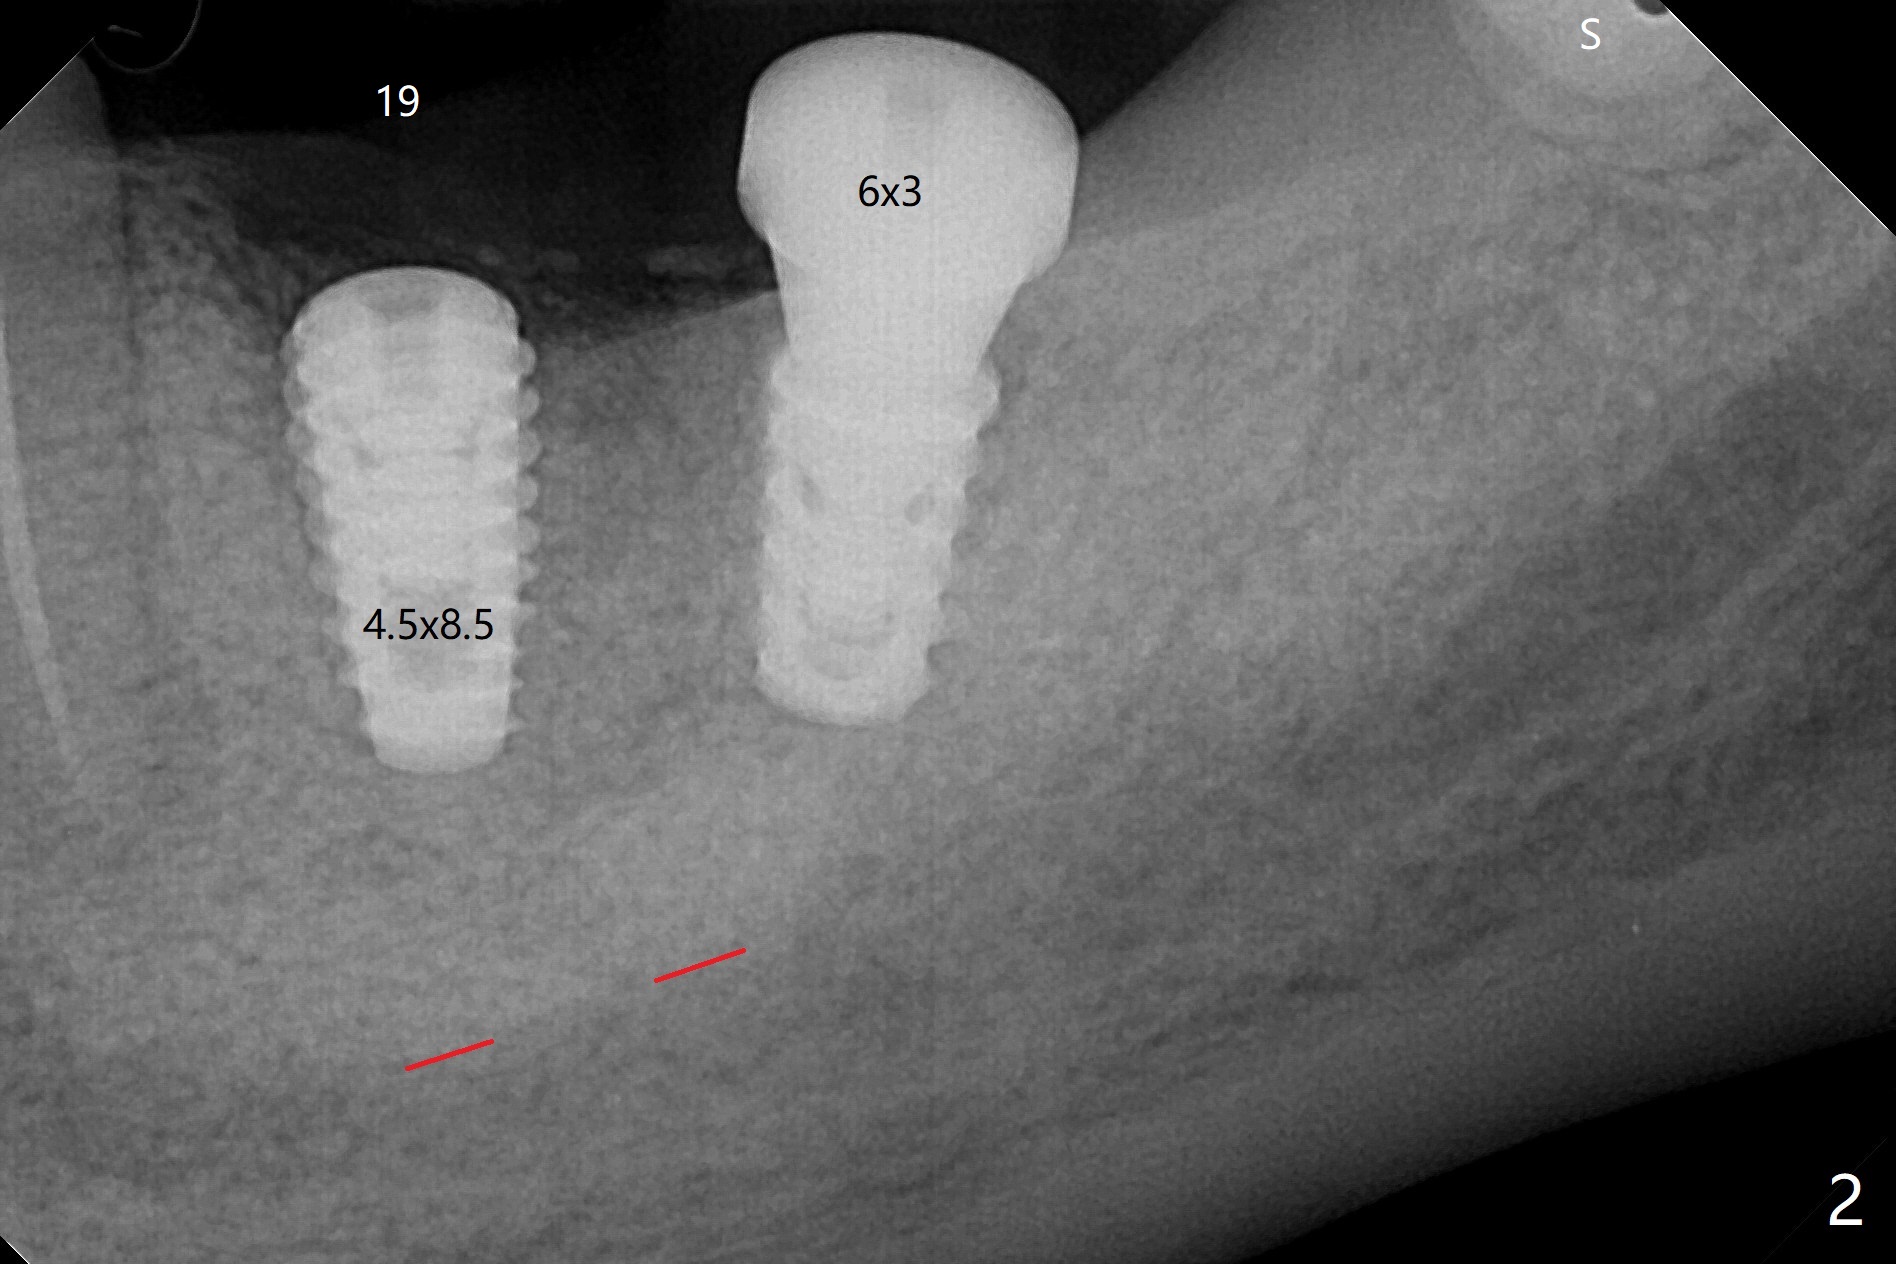

18,19导板远中架在17号牙残根表明树脂(图二:S),起到防止下沉作用,18号牙植体(~35Ncm)使用植体固定钉(fixture anchor mount no stop)植入,后者并且起着固定导板作用,增加19号牙植体植入稳定性,术中根尖片(图一)显示19号牙钻洞还不够深,之后钻头增加长度1.5毫米,4.5x8.5毫米植体扭力15-20Ncm(图二),但是与下齿槽神经管(红色虚线)还有很大距离,可能导板没有完全就位,植入后应该马上再次拍摄根尖片证实植入深度。由于18号牙区角化龈特别狭窄,切开种植,另外一个好处是容易植骨,但是术后疼痛明显,与上前牙即刻植牙(无切开)相比。今后尽量多做即刻种植。不过术后3个月包埋的植体表面有骨质覆盖(图三:*),二期手术很难找到愈合帽,而早些种植的上前牙植体由于过早受力,愈合不佳。当修复基台平面朝向颊侧,基台没有完全就位(图四:>)。当平面面对远中(图五:D),基台好像就位。